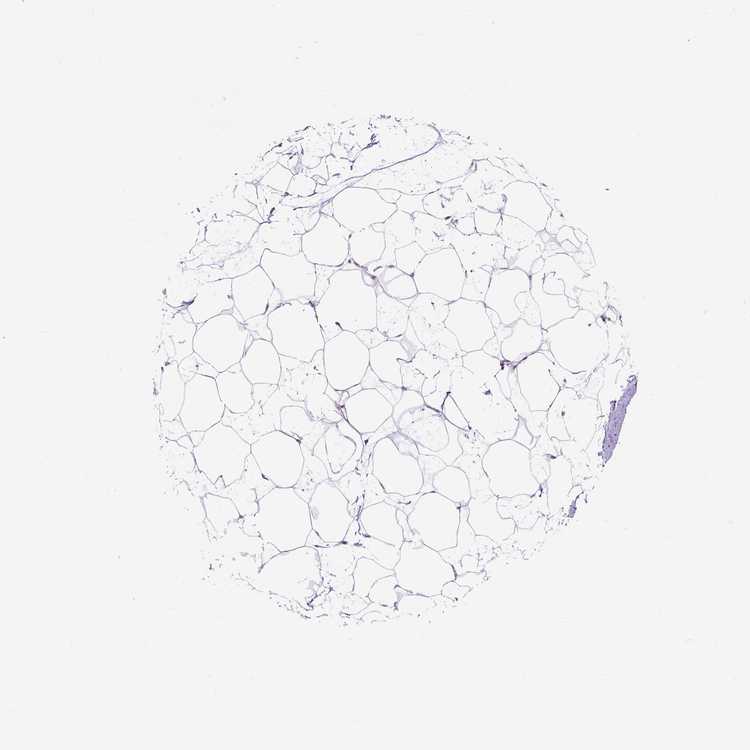

BREAST - Antibody stainingi

Antibody staining in the annotated cell types in the current human tissue is reported as not detected, low, medium, or high, based on conventional immunohistochemistry profiling in selected tissues. This score is based on the combination of the staining intensity and fraction of stained cells.

Each image is clickable and will lead to virtual microscopy that enables deeper exploration of all samples and also displays staining intensity scores, fraction scores and subcellular localization as well as patient and tissue information for each sample.

Antibody HPA042635

Adipocytes Not detected

Glandular cells Low

Myoepithelial cells Not detected